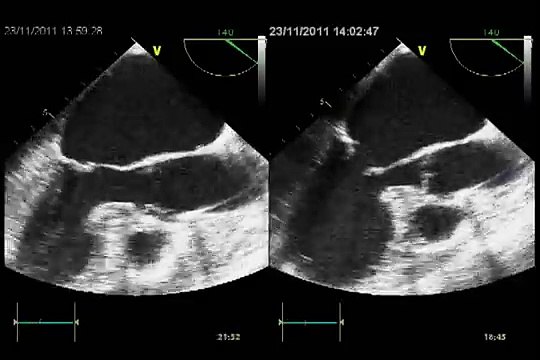

echocardiography, mitral, valve, anatomy, Pérez